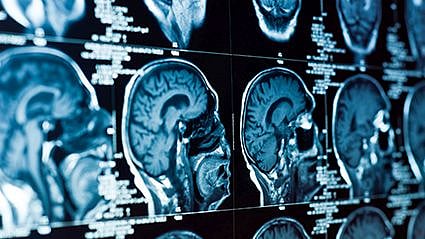

"Dilated perivascular spaces, which are a common MRI finding, especially in the elderly, are not just an incidental finding," said study author Dr. Matt Paradise, a psychiatrist and research fellow at the Centre for Healthy Brain Ageing at the University of New South Wales in Sydney. "Instead, they should be taken seriously, and assessing their severity may be able to help clinicians and researchers better diagnose dementia and help predict the trajectory of people with cognitive decline."

"We all have perivascular spaces. They are natural, but they're usually very small, so small that when we do pictures of the brain, we don't usually see them," explained Dr. Glen Finney, a neurologist at the Geisinger Specialty Clinic in Wilkes Barre, Pa. "Some people have a few enlarged ones that are probably just normal."

Also, the participants had MRI brain scans to look for enlarged perivascular spaces in two key areas of the brain at the start of the study and every two years for eight years.